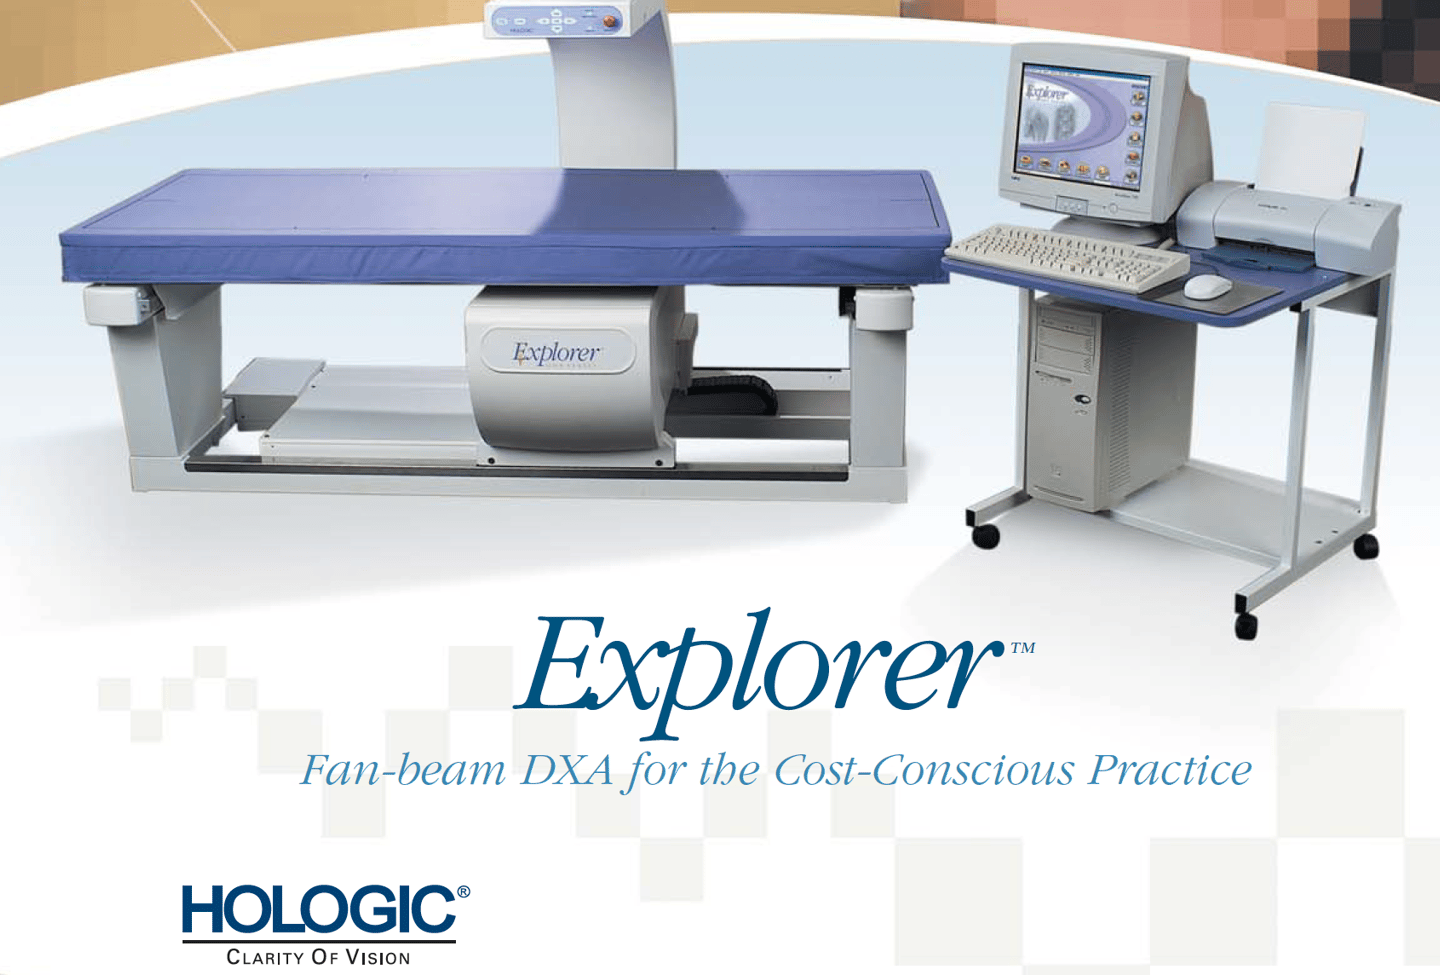

Densitometria para evitar las fracturas sorpresa

DENSITOMETRO

DENSITOMETRIA DEXA DE CADERA Y COLUMNA

Ultrasonido y Densitometría

Estudios de ultrasonido y densitometría para un diagnóstico completo y detallado.